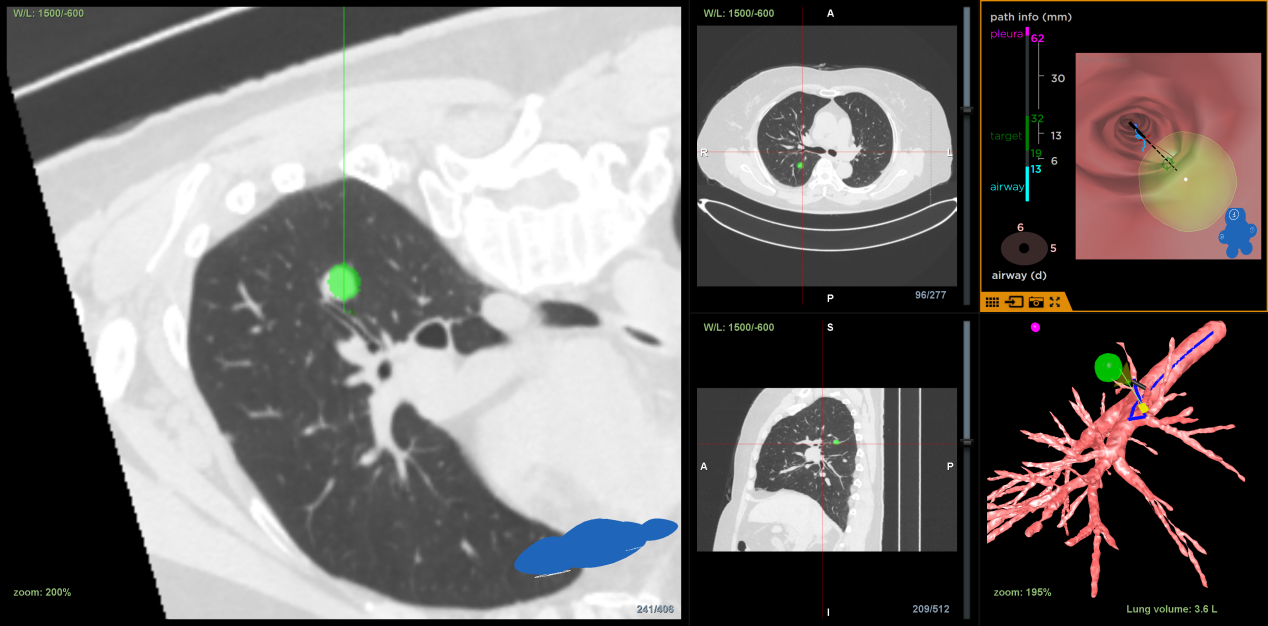

术前,介入团队对患者胸部 CT 进行 LungPro3D 重建,详细描绘出结节、周围血管、邻近支气管的相互位置关系,规划出了一条可以避开血管的相对安全、路径最短的穿刺路径。

在麻醉与围术期医学科的全力支持下,叶小群为患者实施了 LungPro 导航下 BTPNA 术。在导航引导下,支气管镜在 10 分钟内到达病灶位置,叶小群采用一次性支气管镜穿刺活检套装进行穿刺、扩张及鞘管置入,建立 1 cm 隧道后,经超声确认位置理想,立即使用活检嵌顺利取得病灶组织,患者无出血及气胸等并发症。经病理确诊,患者为宫颈转移性腺癌。